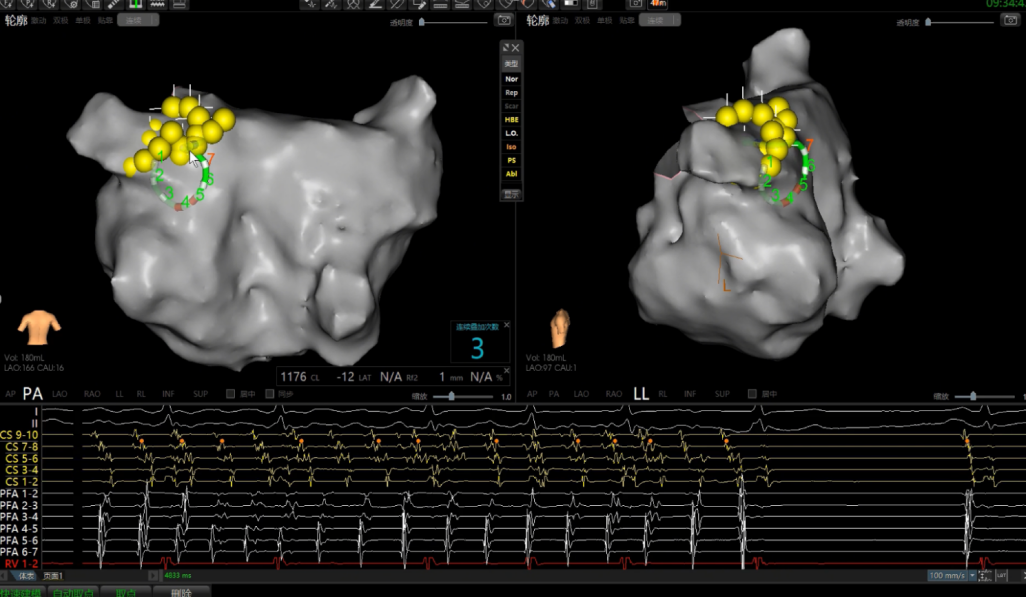

手术在介入导管室的通力配合下进行,姜馨主任、薛建颖主治医师、刘成峰医师密切配合,术中通过右侧股静脉送入心腔内超声(ICE)至右心房,排除左房血栓后成功指导精准房间隔穿刺,沿可调弯鞘管送入锦江心脏脉冲电场消融导管至左房,构建左房三维解剖模型并行基质标测,标测显示左房基质尚可,分别行左侧、右侧肺静脉消融。消融参数:1800v、400ms、400μs,共放电消融148次(消融左上肺静脉时转复为窦性心律),验证双肺静脉均隔离。术后重新标测显示所有肺静脉均已急性阻滞,消融效果理想,肺静脉前庭损伤范围也达到了预期的标准,同时ICE监测未见明显心包积液。手术仅用时30分钟,时间明显缩短,手术过程精准高效。术后患者恢复情况良好并顺利出院。术后1月复查心电图提示窦性心律,心脏超声提示心脏较前明显缩小,收缩功能明显改善,射血分数由25%提升至40%,心功能标记物NT-proBNP 恢复正常,仅54pg/ml。

图2 放置冠状窦十级后心腔内电图所示房颤波

图4 PFA于左上肺静脉消融时转为窦率,继续消融